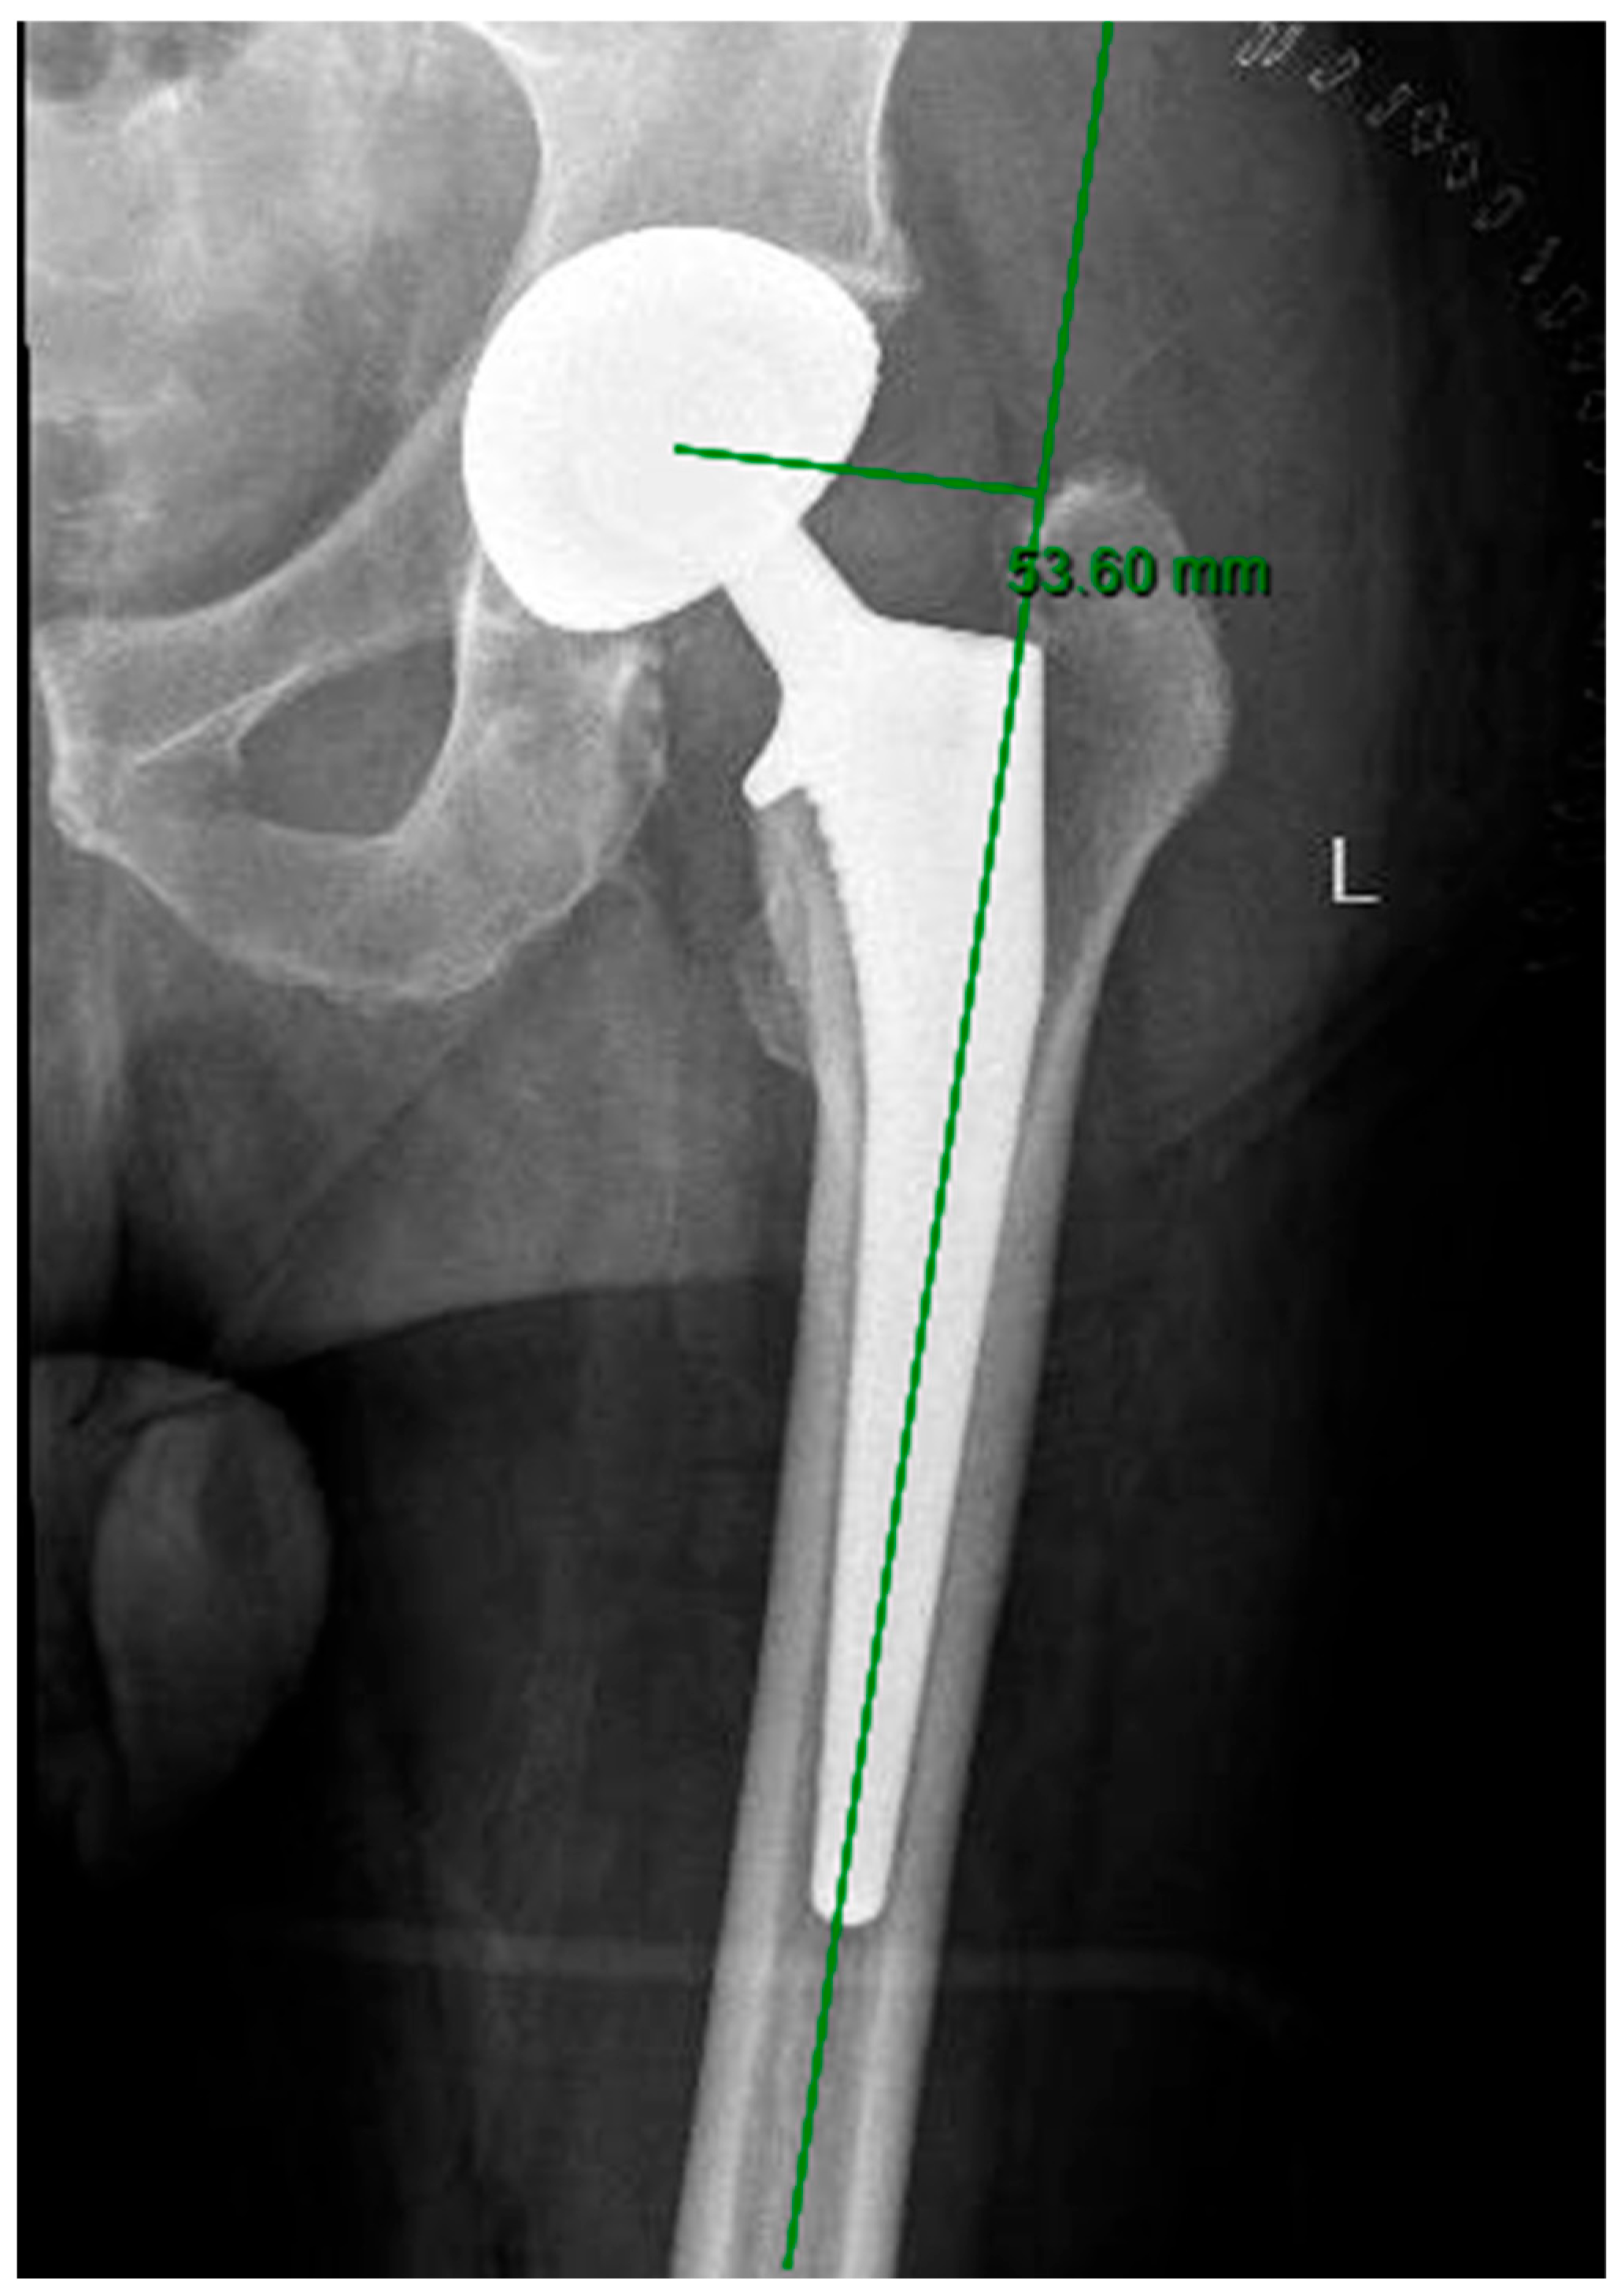

- Kumar, P.G.A.; Kirmani, S.J.; Humberg, H.; Kavarthapu, V.; Li, P. Reproducibility and accuracy of templating uncemented THA with digital radiographic and digital TraumaCad templating software. Orthopedics 2009, 32, 815. [Google Scholar] [CrossRef] [PubMed]

- Lecerf, G.; Fessy, M.H.; Philippot, R.; Massin, P.; Giraud, F.; Flecher, X.; Girard, J.; Mertl, P.; Marchetti, E.; Stindel, E. Femoral offset: Anatomical concept, definition, assessment, implications for preoperative templating and hip arthroplasty. Orthop. Traumatol. Surg. Res. 2009, 95, 210–219. [Google Scholar] [CrossRef] [PubMed]

| Mean Femoral Offset, mm (SD) | 44.92 (7.34) | 45.31 (5.88) | 0.697 |